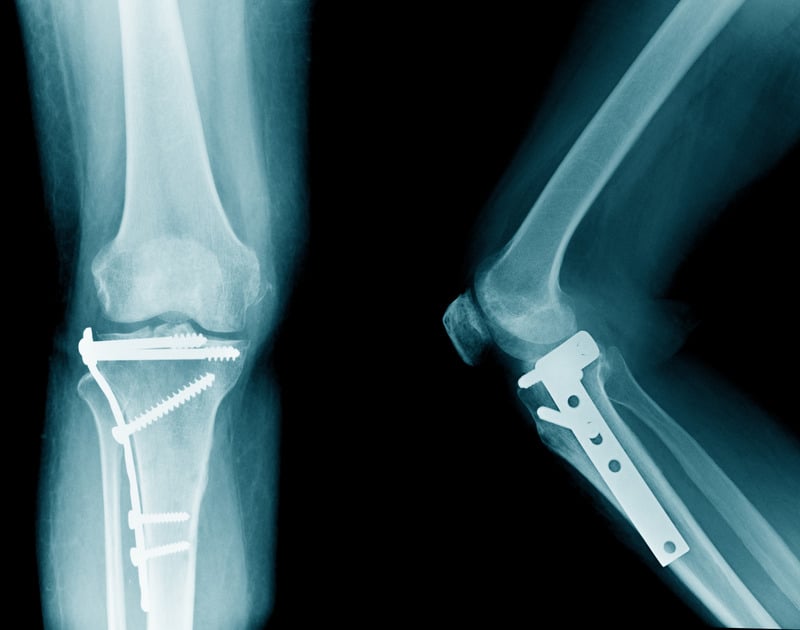

• Εσωτερική Σταθεροποίηση (Οστεοσύνθεση): Αυτή η μέθοδος περιλαμβάνει την τοποθέτηση μεταλλικών πλακών, βιδών ή ράβδων για να

σταθεροποιηθεί το κάταγμα εσωτερικά. Η ακριβής ευθυγράμμιση των οστών επιτρέπει την ταχύτερη και πιο σταθερή επούλωση.

Αποκατασταση γονάτου